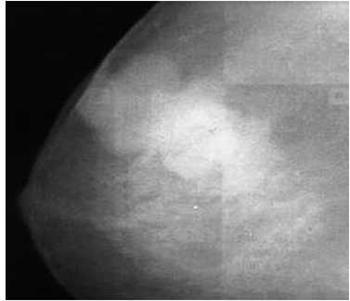

Другим примером является прямая радионуклидная

цистография. Методика исследования включает катетеризацию уретры, ретроградное

заполнение мочевого пузыря физиологическим раствором хлорида натрия, смешанного

с меткой, и получение с помощью гамма-камеры изображений области мочевых путей

во время заполнения пузыря, в момент мочеиспускания и после него. Полученное

изображение приведено на Рис. 3.

Рисунок 3 - Радионуклидная диагностика мочевого

пузыря.